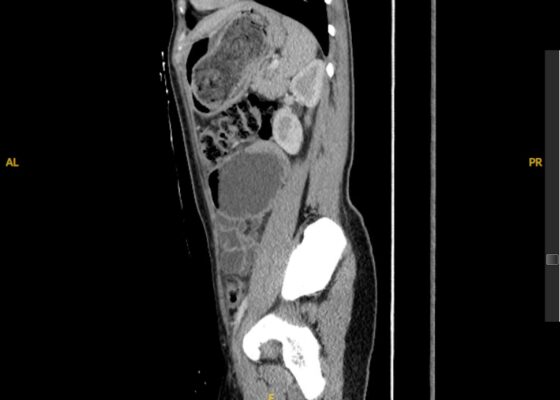

DOI: https://doi.org/10.5070/M5.52309Computed tomography (CT) of the abdomen and pelvis demonstrated pleural effusions in the lung bases (blue stars), ascites (blue stars), and enlarged ovaries with multiple cysts/follicles (white arrows). A formal pelvic US also demonstrated large volume ascites (white diamonds) and bilateral ovarian enlargement with numerous cysts. A CT angiogram (CTA) of the chest demonstrated small bilateral pleural effusions and no obvious pulmonary embolism.